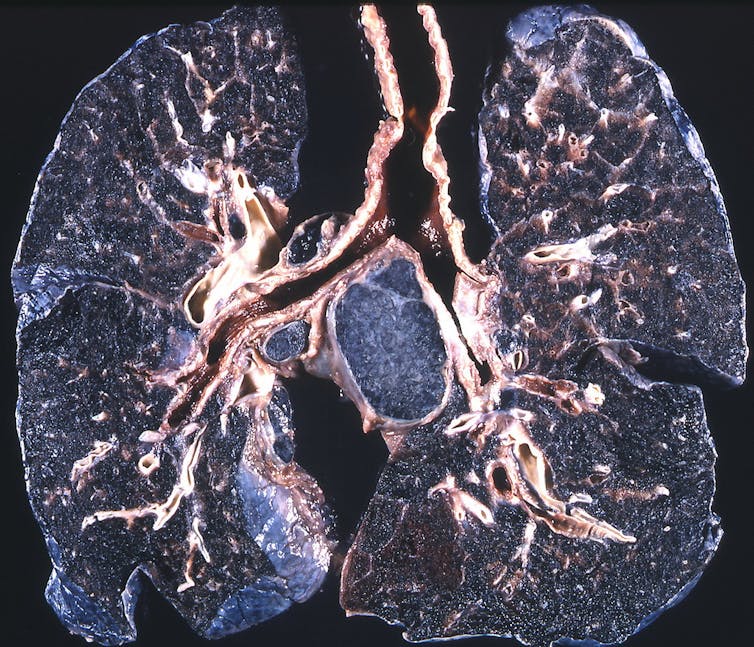

Surface and underground mining is associated with two pneumoconioses, or dust diseases of the lung. Black lung disease, also known as coal workers’ pneumoconiosis, comes from inhaling coal mine dust. The other disease, silicosis, is caused by inhaling silica dust from crushed rocks. Black lung and silicosis often appear together because coal seams are found between rock layers that contain silica.

When miners inhale dust, it deposits along their airways. Their bodies try to remove the dust by sending in special white blood cells called macrophages to engulf and chemically digest it. But the cells are unable to break down the dust, so they die and release enzymes that damage lung tissue. This causes problems that include chronic bronchitis, emphysema and fibrosis (scarring). In progressive massive fibrosis, the most severe version of black lung, scarring causes lung volume to shrink, further damaging adjacent lung tissue and making air exchange even worse.